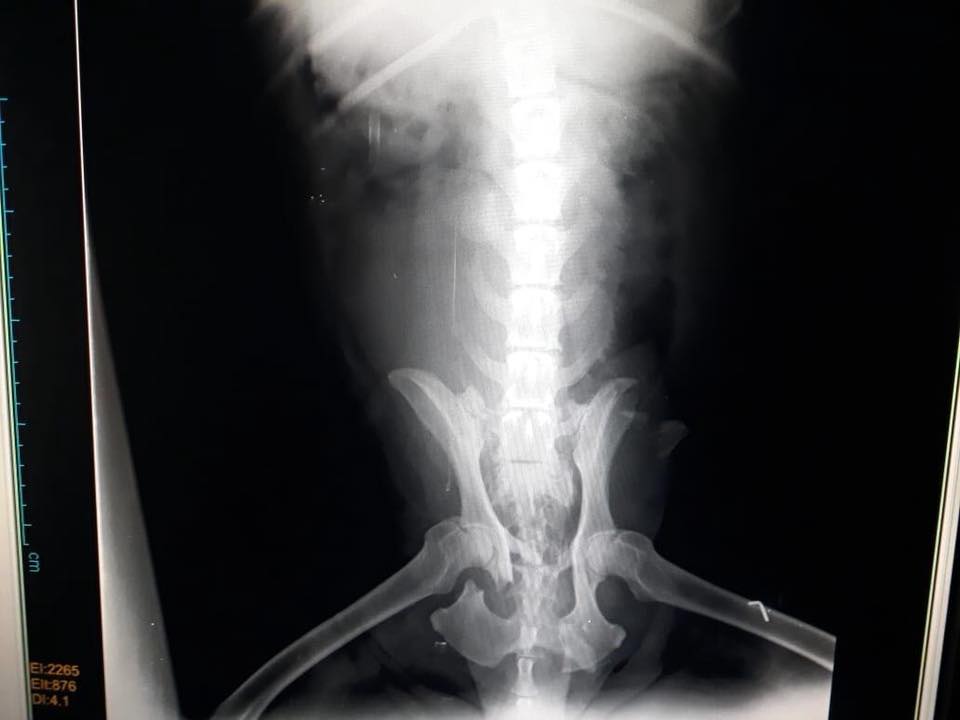

His spine is broken and will never stand on his own. We are using wheel cart on him so that he walks at least